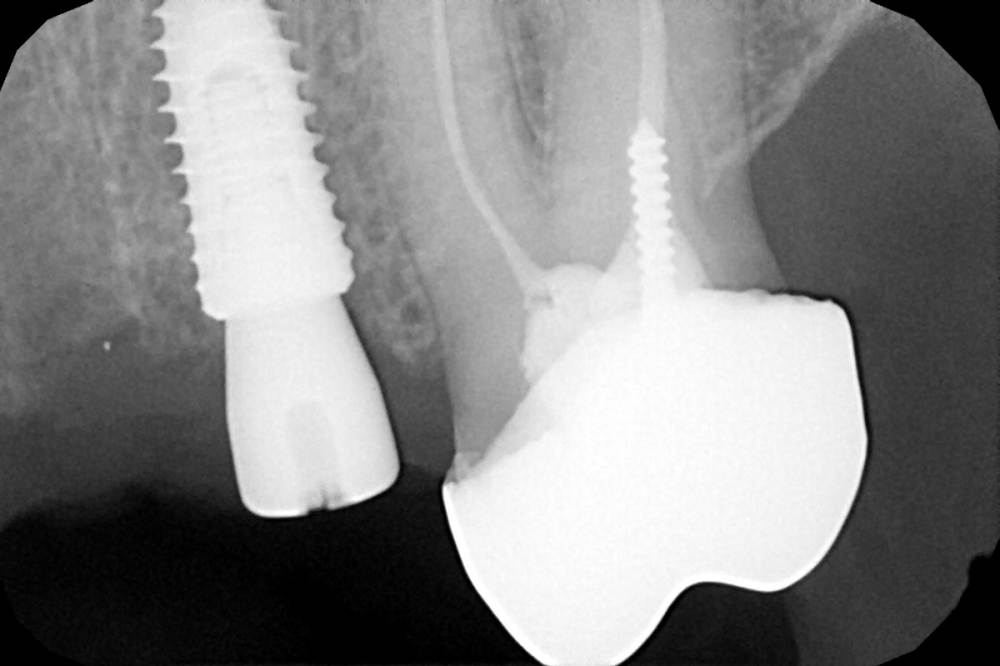

Женька Опубликовано 19 апреля, 2021 Автор Поделиться Опубликовано 19 апреля, 2021 Rg Ссылка на комментарий

Женька Опубликовано 21 июля, 2021 Автор Поделиться Опубликовано 21 июля, 2021 3 месяца минуло... клык на торке 30 неприятные ощущения второй премоляр на 10 и подвижность... отправил на кт. Всё насмарку... Ссылка на комментарий

Борис80 Опубликовано 21 июля, 2021 Поделиться Опубликовано 21 июля, 2021 премоляр в любом случае недозаглубитом болеет... Ссылка на комментарий

Женька Опубликовано 2 августа, 2021 Автор Поделиться Опубликовано 2 августа, 2021 2.5 с тупым перкуторным звуком И вишенка, нет АРБУЗИЩЕ, на торте 2.3 в соседней теме в ортопедии посоветовали перестать уничтожать людям зубы, тоже самое помоему можно сказать и по хирургии... Правильно же понимаю, что протезировать такой (2.3) не стоит. Даже если торк выдержит в 35 чревато проблемами после установки постоянной ортопедии. Ссылка на комментарий